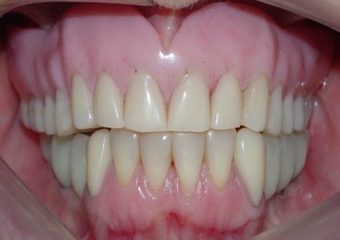

Imagens da prótese fixa superior em porcelana sobre implantes Cone Morse

Sorriso final do caso terminado em março de 2012